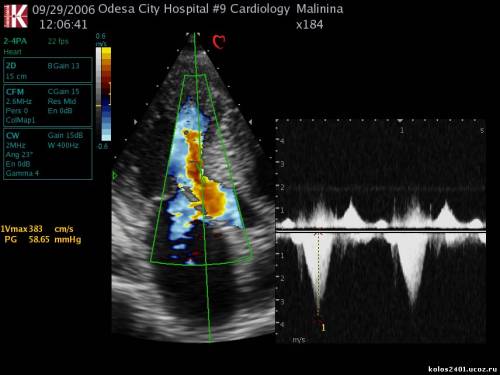

ГКПМ- признаки обструкции выносящего тракта ЛЖ - градиент давления в выносящем тракте ЛЖ=58 мм рт ст